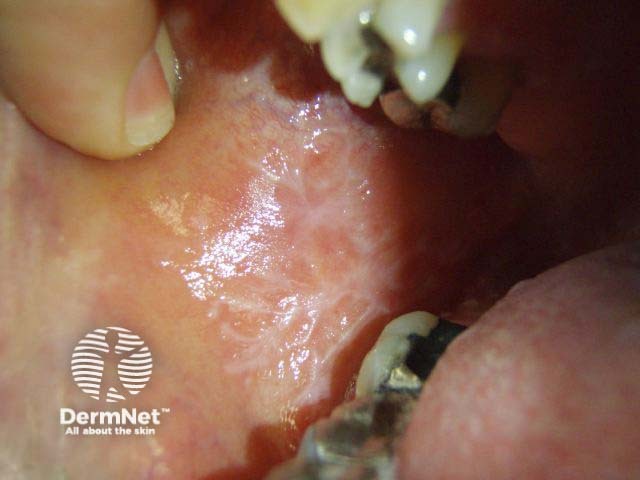

Name this lichenoid skin condition.

Lichen planus

How would you treat them?

Lichen planus is a mucocutaneous disorder in which there are multiple pruritic, firm, polygonal and violaceous plaques. White reticular streaks are commonly noted in the buccal mucosa. Treatment depends on the extent of the disorder; topical steroids may require supplementing with oral steroids or immunomodulatory medication.